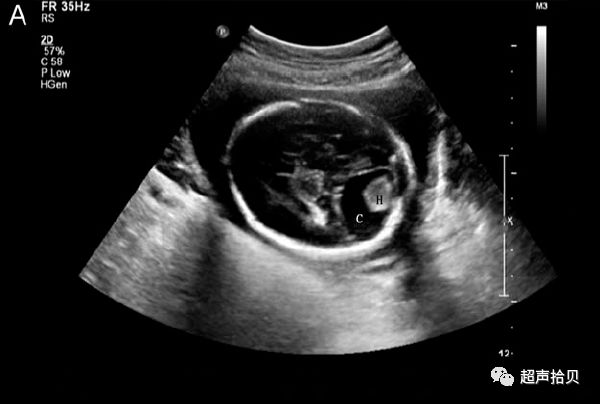

图4:图4A,25次妊娠时获得的横向声像图。 病变最初被诊断为蛛网膜

囊肿(C)伴有出血(H)。 B,妊娠26孕妇的产前MRI T2加权横向图像显示硬脑膜窦性畸形(D)合并血栓形成(T)